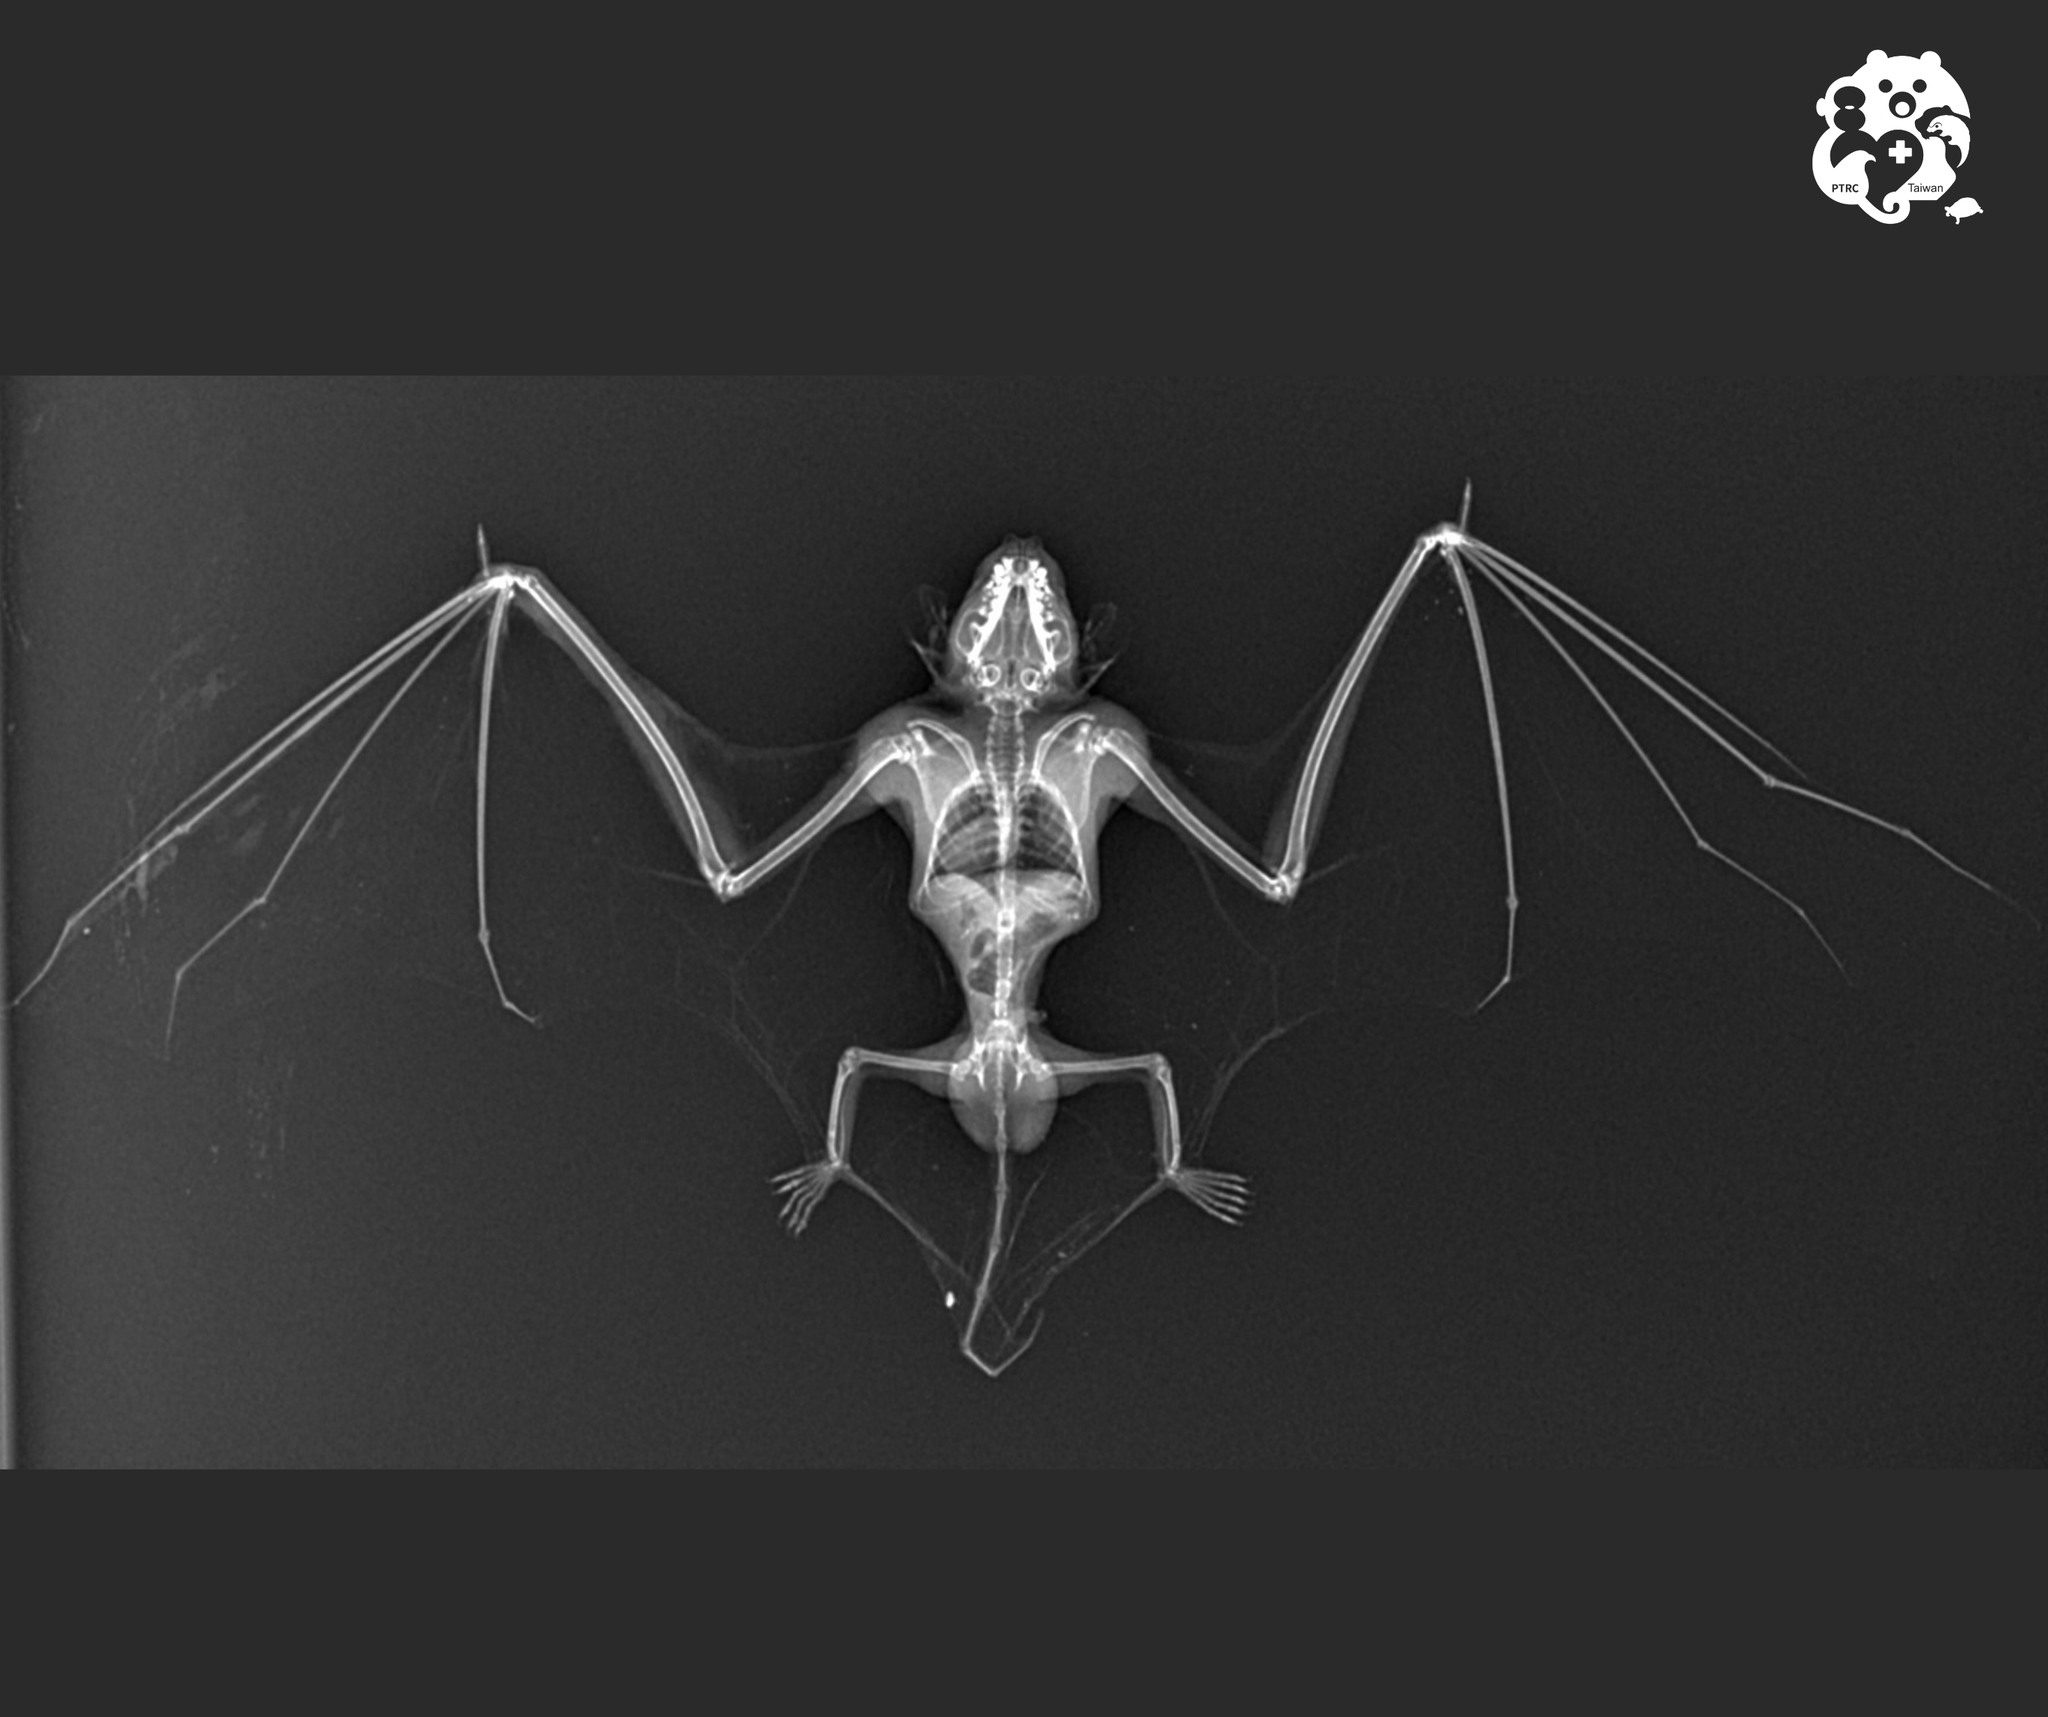

-【高頭蝠】

最後來一個應景的照片~也是本次的壓軸~高頭蝠! ![]() ,特化的手指非常細長,連獸醫看到都嘖嘖稱奇呢!

,特化的手指非常細長,連獸醫看到都嘖嘖稱奇呢!